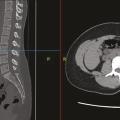

Les recommandations de la Haute Autorité de santé (HAS) publiées en 2019 ont reconnu la diminution de la force et/ou de la masse musculaire comme un critère phénotypique de la dénutrition.1 Parmi les outils recommandés chez l’adulte de moins de 70 ans figure l’évaluation de la surface musculaire en imagerie scanner. Néanmoins,…